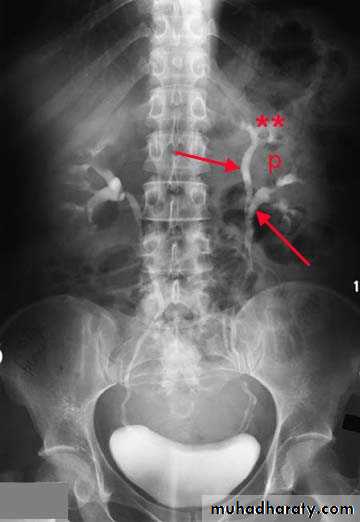

IVU shows :

The kidneys at low position .

Close to the spine with long axis parallel to the spine .

Mal–rotation manifested by medially directed calyces.

The renal pelvis and ureters are anterior and lateral in position .

HORSE –SHOE KIDNEY

HORSE SHOE KIDNEY